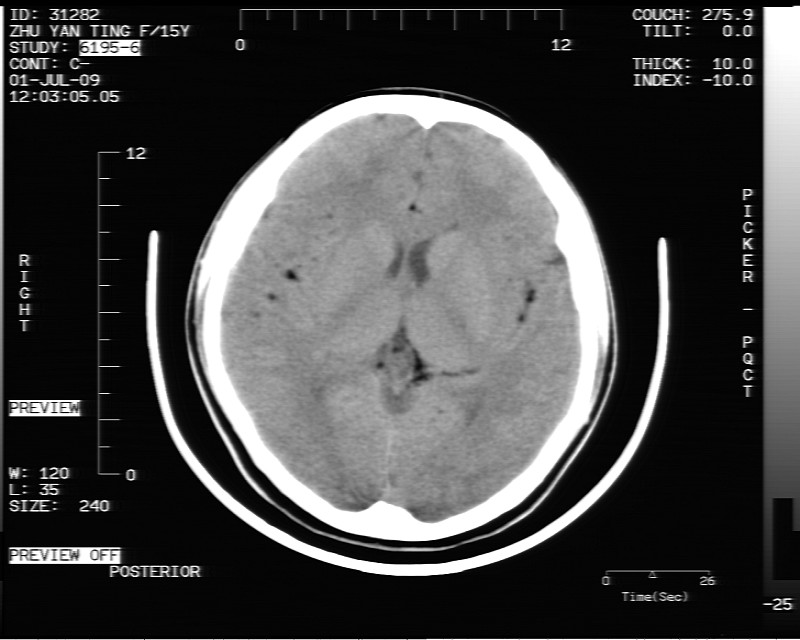

以下是引用随光逐影在2009-7-1 16:26:00的发言:[br]鞍上池表皮样囊肿或含脂肪类肿瘤破裂并化学性脑炎?

以下是引用余辉在2009-7-1 17:20:00的发言:[br]病变ct值-20至-80[br]考虑脑内脂肪瘤破裂,瘤主体应该在右侧桥小脑角池及鞍上池[br]鞍上池病灶面积较大,ct值应该能够测准,应此病灶应该就是脂肪密度,病灶密度有ct值-20至-80hu,为成熟脂肪密度,因此考虑脂肪瘤,也不除外其他含成熟脂肪的病灶[br]皮样囊肿密度应该稍高一点

以下是引用zjzjr在2009-7-1 16:52:00的发言:[br]支持皮样囊肿破裂.,表皮样囊肿一般密度均高.[br][br][本贴已被 zjzjr 于 2009-7-1 16:52:29 修改过]